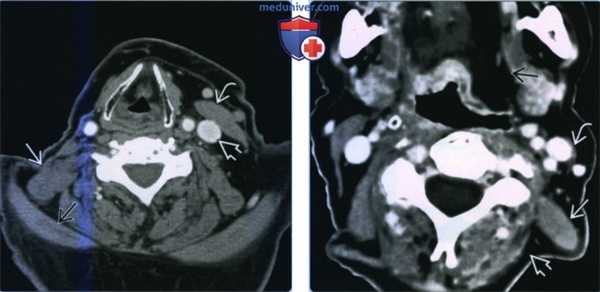

(Слева) МРТ Т1ВИ, корональный срез: при визуализации обеих нижних конечностей определяется диффузное увеличение размеров правой икроножной мышцы. На этой томограмме усилена интенсивность внутримышечного сигнала, обусловленная увеличением объема внутримышечной жировой ткани. Такая картина характерна для псевдогипертрофии.

(Справа) MPT STIR, корональный срез: у этого же пациента определяется повышение интенсивности внутримышечного сигнала в правой икроножной мышце. Такие отечные изменения наблюдаются как при истинной гипертрофии, так и при псевдогипертрофии.